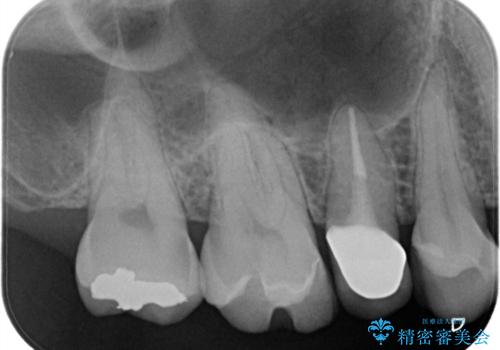

【セラミックインレー】虫歯の治療

- 虫歯を認めたため、セラミックインレーにて治療を行いました。

見た目も綺麗に修復することができ患者様には満足していただきました。

セラミックインレーの接着には必ずラバーダム防湿を行なっています。